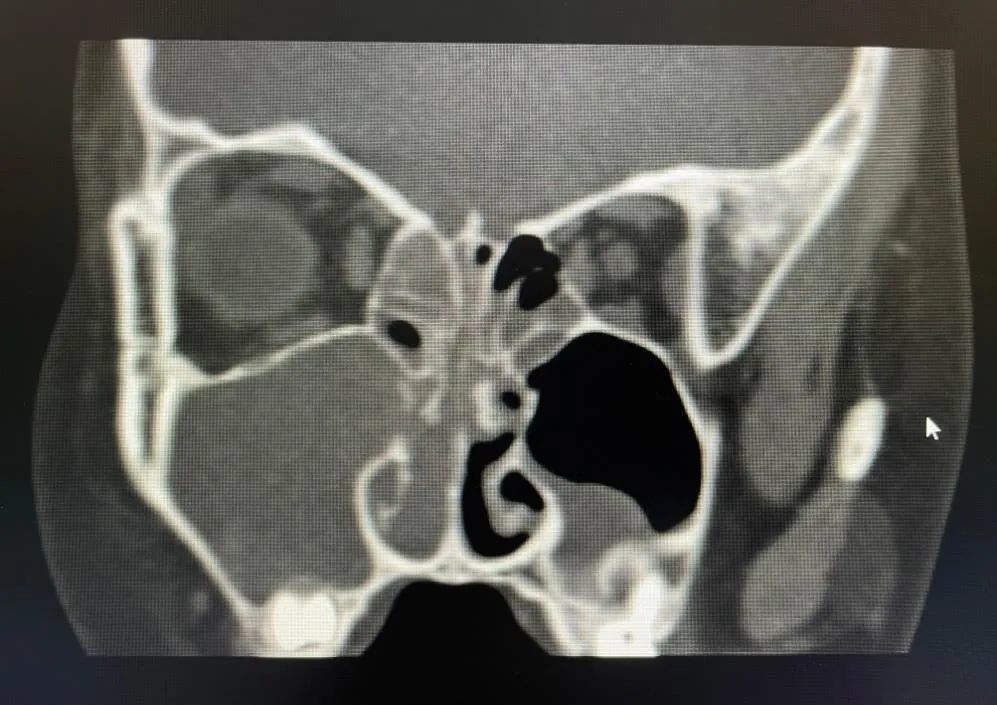

进一步检查,CT进一步验证了王主任的诊断,萱萱的确患有鼻息肉,而且是出血性鼻息肉,同时患有右侧鼻窦炎。